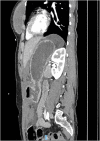

Presentation of case: Our patient is a 35-year-old female who was a restrained front seat passenger in a car vs. tree collision at 80 km/h. Her seat belt was worn with the shoulder strap under her left axilla. She sustained multiple injuries including complete transection of the gastroduodenal junction. In addition to this she had splenic, liver, transverse colonic, left lower rib and humeral injury. She underwent damage control laparotomy with splenectomy; re-look with gastrojejunostomy and transverse colonic resection with defunctioning ileostomy. She made a good recovery and was discharged after a 4 week admission.